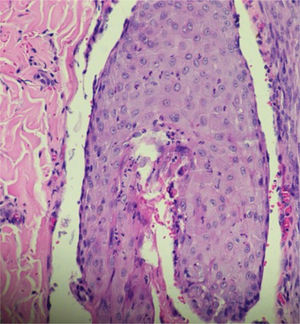

Paciente do sexo feminino, 26 anos, primigesta, no curso de 31 semanas de gestação, relatava aparecimento de lesões cutâneas pruriginosas no tronco, com dois meses de evolução. Ao exame físico, observavam‐se pápulas eritematosas e pústulas localizadas no abdome (em especial na linha nigra), no esterno, dorso e na face lateral dos glúteos (figs. 1 e 2). Foram solicitados exames laboratoriais e realizada biópsia de pústula do dorso. Os exames laboratoriais não revelaram anormalidades, e a análise histopatológica evidenciou infiltrado perivascular predominantemente linfocítico na derme, além de folículo piloso permeado por infiltrado inflamatório com predomínio de neutrófilos e destruição da estrutura folicular (figs. 3 e 4). A paciente foi tratada com gel de peróxido de benzoíla a 5% e apresentou regressão completa das lesões na primeira semana pós‐parto.